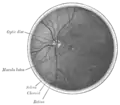

Cross-section of human eye, with choroid labeled at top.

Interior of anterior half of bulb of eye. (Choroid labeled at right, second from the bottom.)